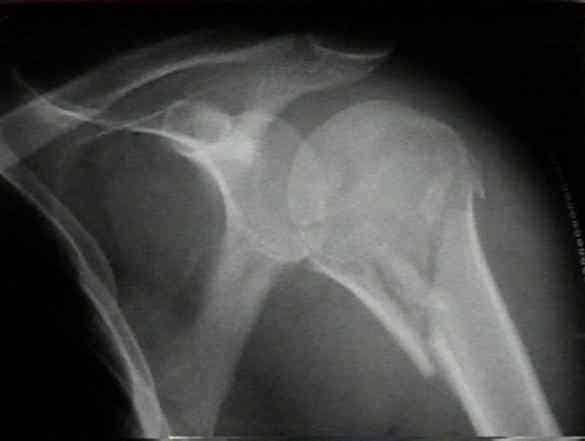

Самая информативная процедура — рентген. Снимки выполняют в двух проекциях — аксиальной, сверху вниз через подкрыльцовую ямку, и в прямой. Дополнительно, при необходимости уточнения данных по травме, может быть назначена компьютерная томография.

Внутрисуставные переломы подтверждают на ультразвуковом исследовании. Снимки плечевой кости в аксиальной проекции устанавливают наличие боковых смещений отломка. Рентгеновские фото помогают диагностировать и отличить вколоченный перелом плечевой кости от невколоченного.